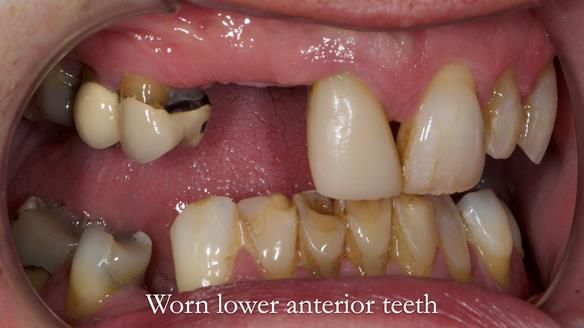

Case Overview: Brian was referred to me for specialist prosthodontics by his general dentist.

- Bruxism: The upper and lower teeth are worn and chipped due to heavy clenching and grinding. With a powerful bite and limited space for replacement teeth, dental implants supported fixed teeth are not recommended. A simpler solution is a metal-based partial denture/splint (“Combat denture”) as planned below. This will act as a splint to protect and replace the missing teeth.

- Lower Front Teeth: These can be restored to improve their appearance and protect them from further wear. I recommend this treatment but it’s optional and would be done after fitting the upper denture.

Treatment Process: I provided the clinical work, while Rowan Garstang handled the technical work. The treatment required five visits to fit the RPD. The worn lower anterior teeth were then built up. Unfortunately, I did not check the guidance on the denture teeth after this, and tooth 11 fractured off the denture. Brian was very understanding, and I adjusted the denture thoroughly. It has been fracture-resistant and trouble-free for the last three years.